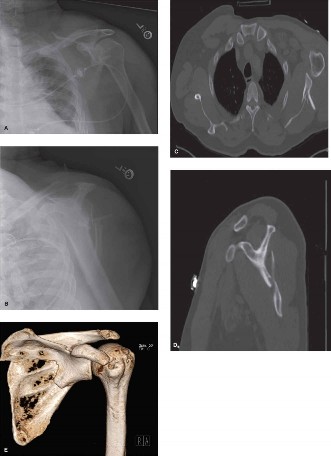

* Figure 2: Intraoperative image demonstrating stable internal fixation of a scapular neck and body fracture with a contoured locking plate along the lateral border of the scapula. Note the screw trajectories and soft tissue protection.